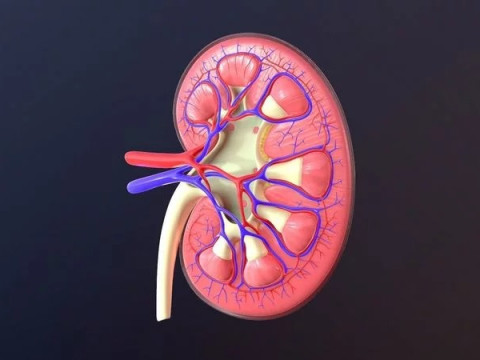

Human Kidney Low-poly Modelo 3D

Human Kidney Modelo 3D blend, jpg, fbx, max, De jack2024

human kidney renal urine organ anatomical health people anatomy biology urinary system electrolytes internal organs science medical crossNo hay comentarios sobre este artículo.